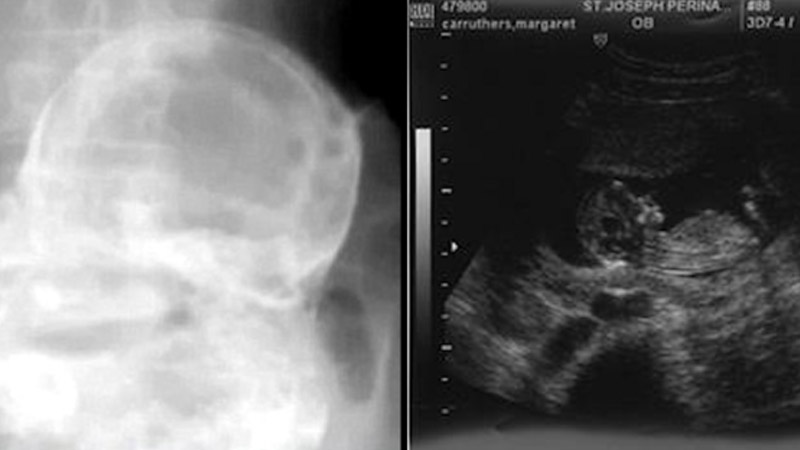

A Brazilian woman in her 80s who went to the hospital with stomach pains had a fetus in her uterus that was 44 years old. A doctor in the central Brazilian state of Tocantins did an X-ray on the woman’s stomach and found a “stone baby.”

The X-ray showed “the face, the bones of the arms, the bones of the legs, the ribs, and the spine” of a baby that died between 20 and 28 weeks.